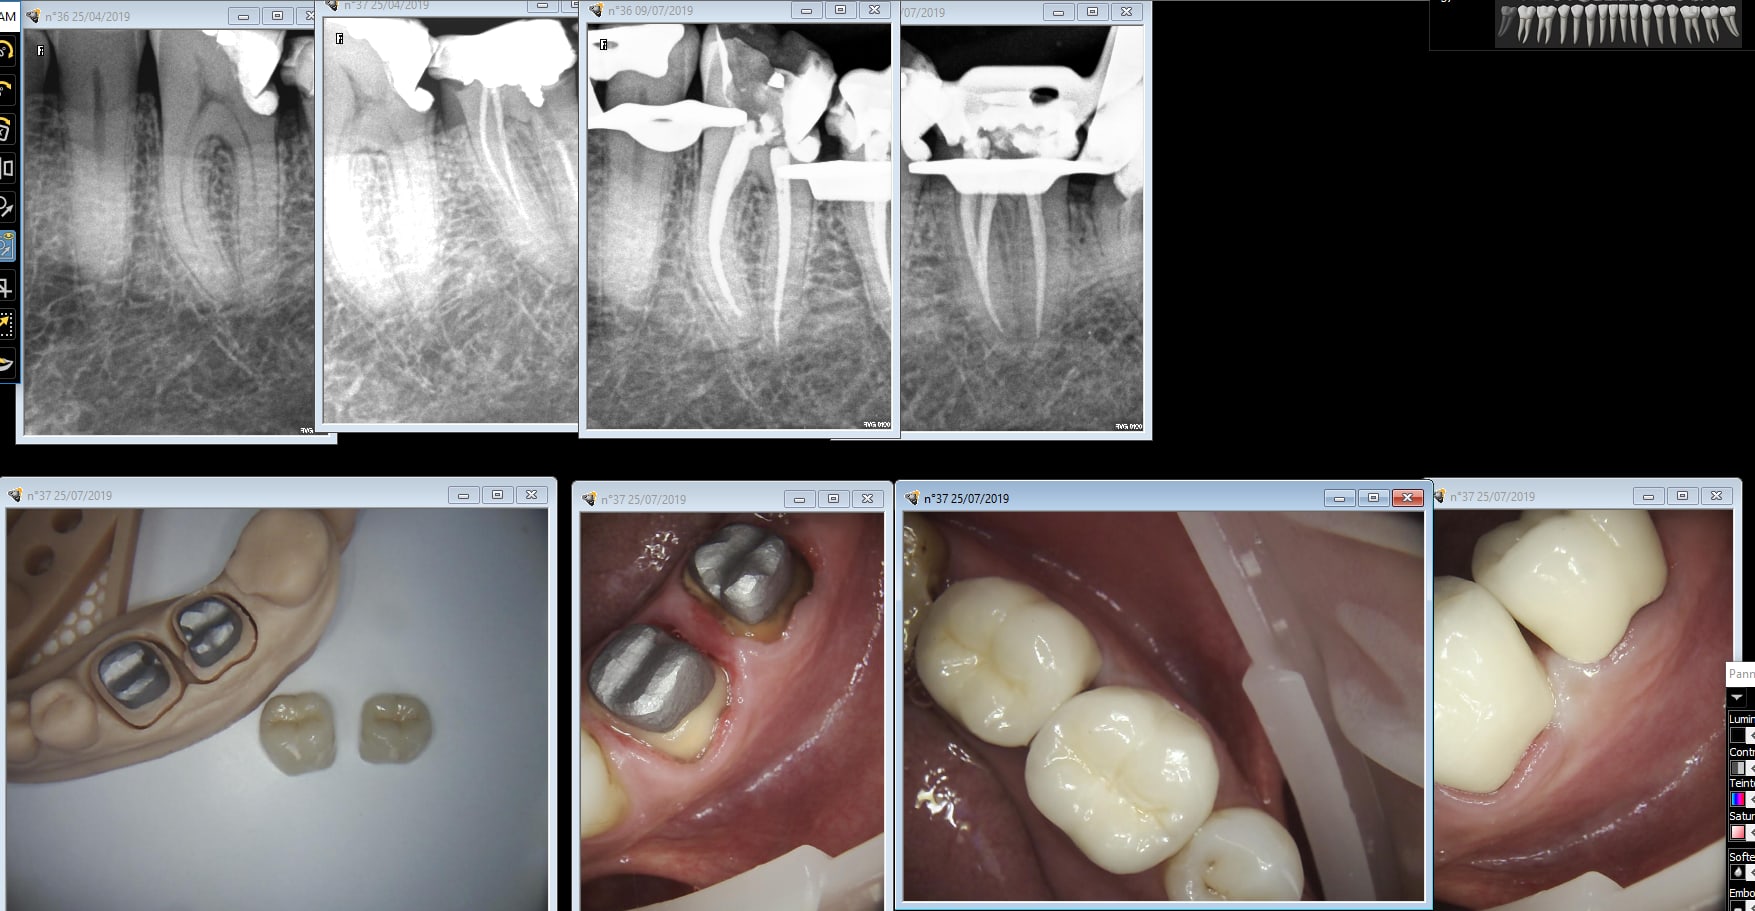

Gouezin 36 37 uzyys9 - Eugenol

One shot CMU made in china. 0 retouche. Photos des piliers après essayage 0 saignement.